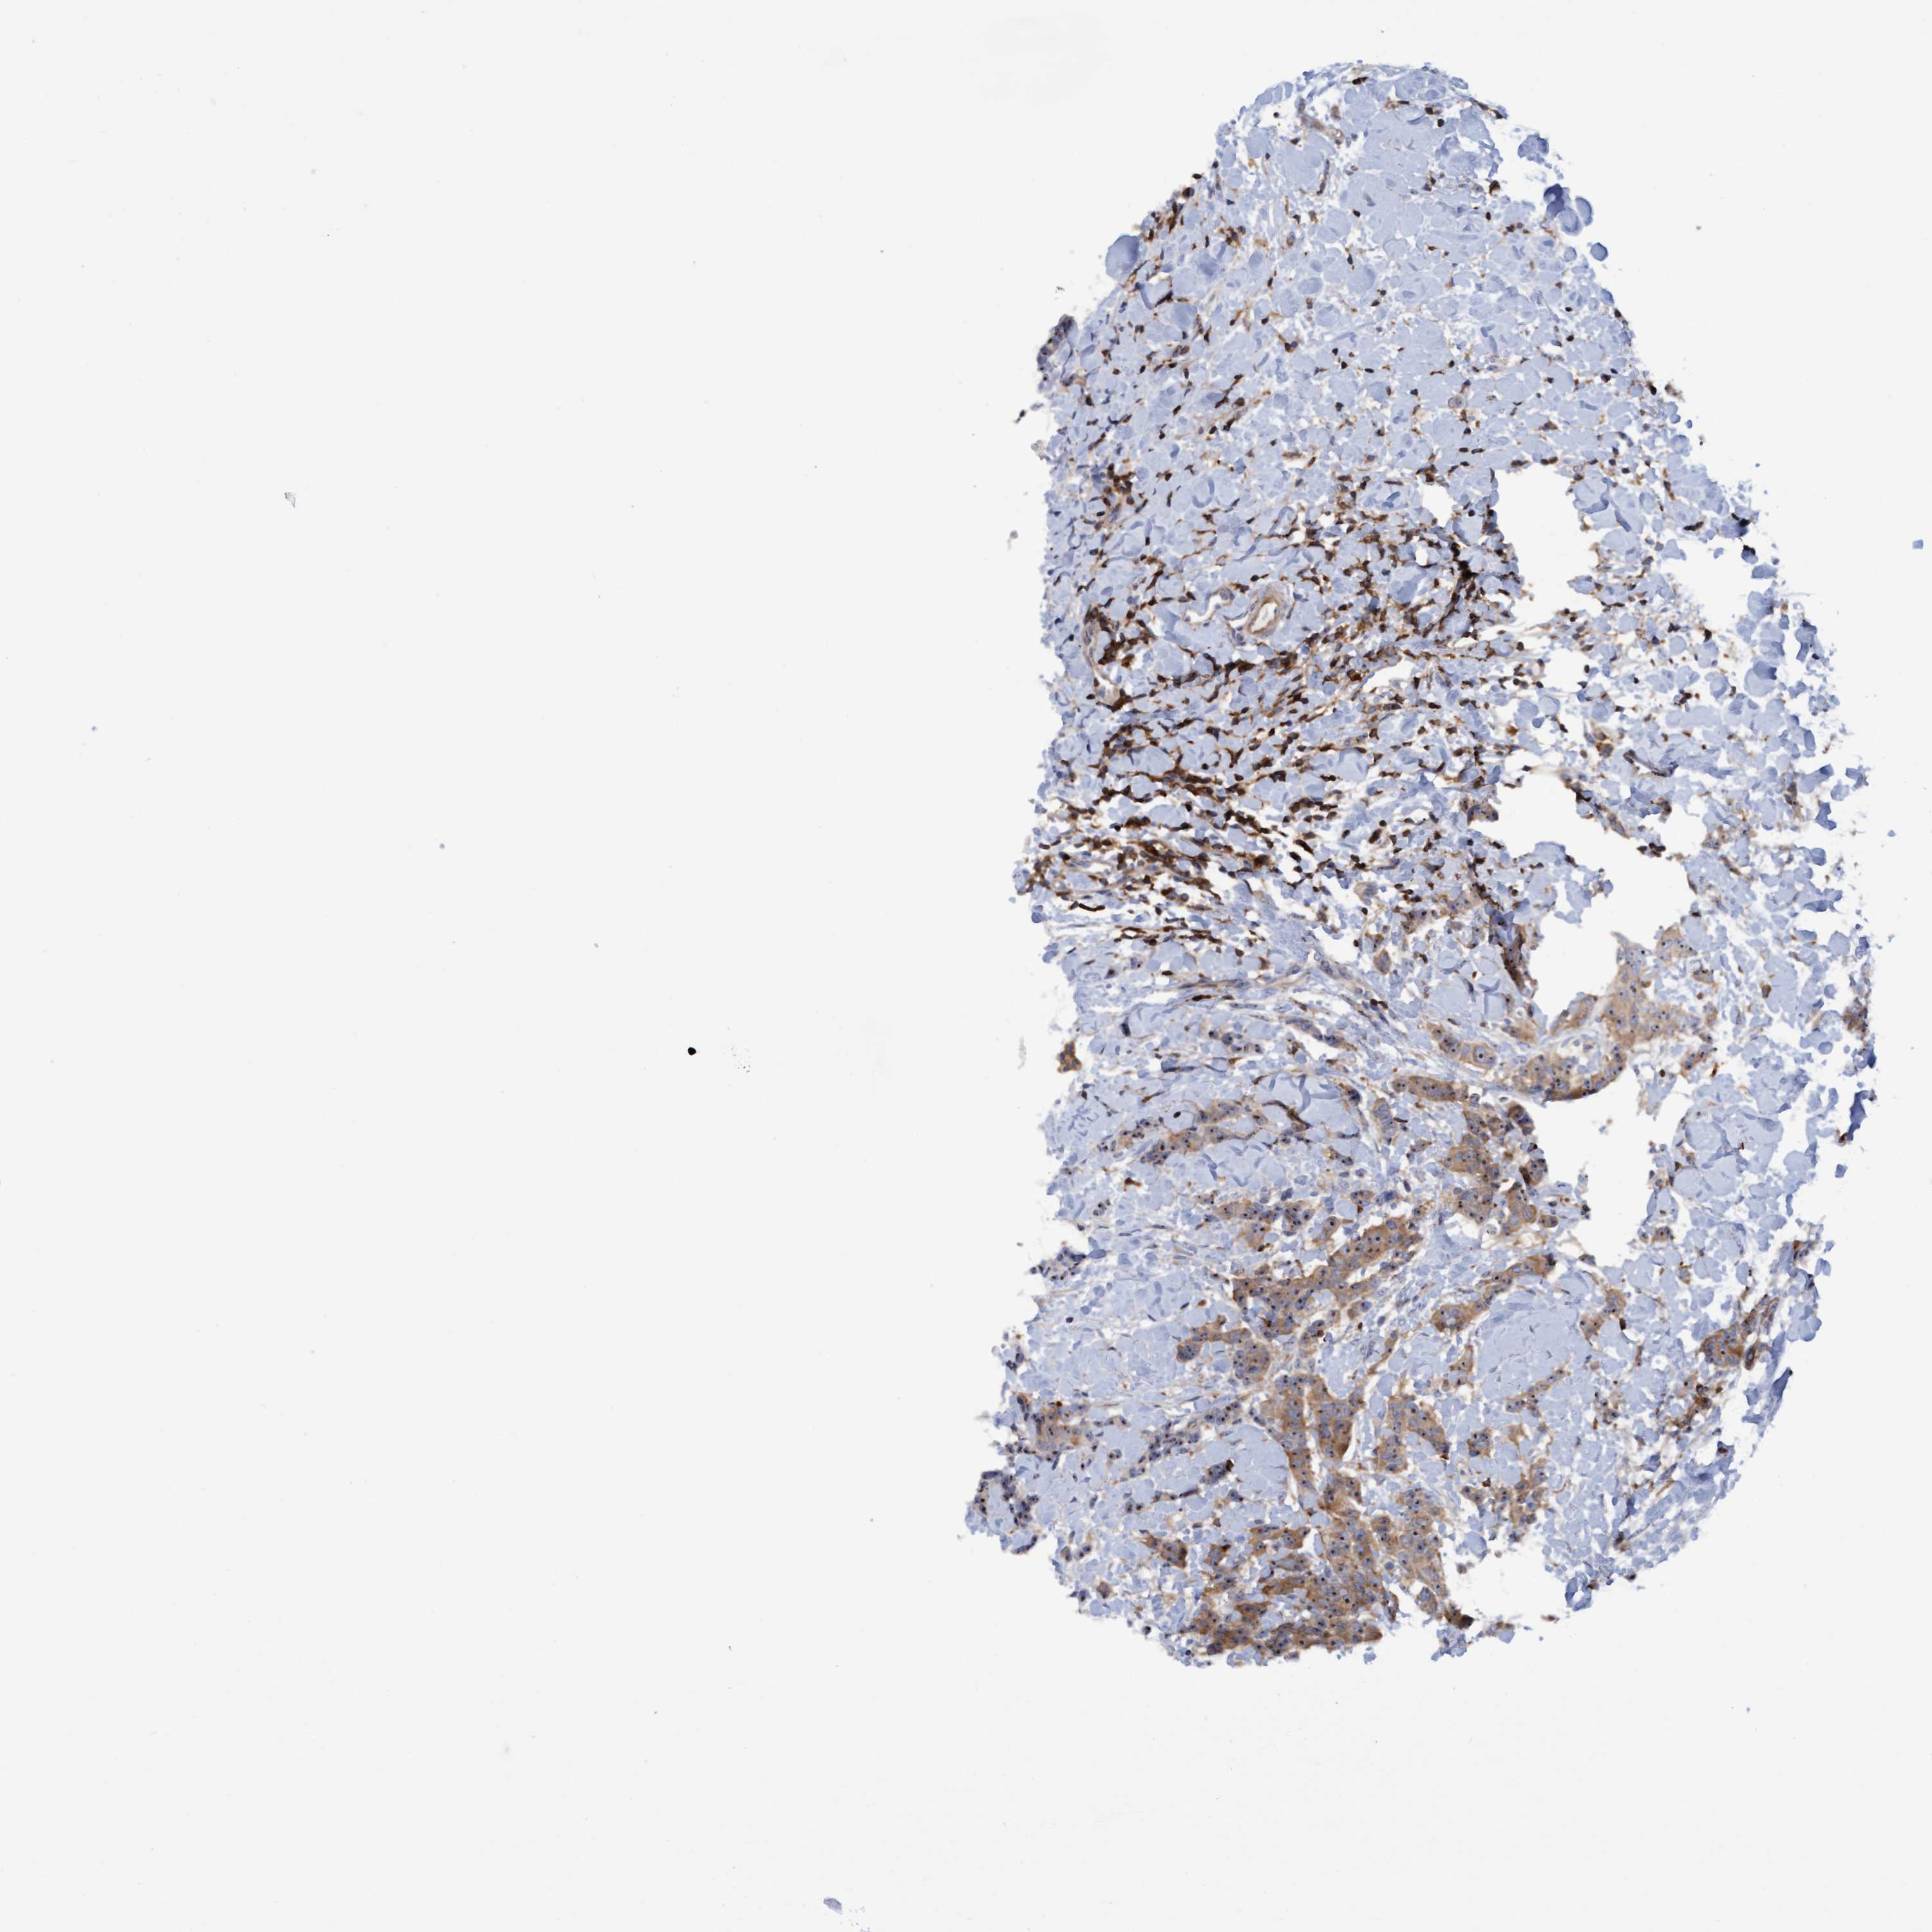

BRCA TCGA BRCA VALIDATION PROTEIN EXPRESSION

TCGA RNA samplesi

RNA-seq data is reported as average FPKM (number Fragments Per Kilobase of exon per Million reads), generated by the The Cancer Genome Atlas (TCGA) .

Normal distribution across the dataset is visualized with box plots, shown as median and 25th and 75th percentiles. Points are displayed as outliers if they are above or below 1.5 times the interquartile range. FPKM values of the individual samples are presented next to the box plot.

Average pTPM 22.5

Number of samples 1022